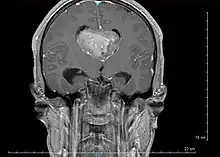

Le diagnostic est réalisé grâce à l'imagerie cérébrale, scanner ou au mieux IRM cérébrale, retrouvant cette formation hétérogène à trois composantes en général (tissulaire +/- kystique et calcique), avec rehaussement partiel à l'injection de produit de contraste.

Elle permet d'étudier les rapports avec les zones fonctionnelles du cerveau (notamment le pilier du fornix, un des composants du circuit de Papez responsable de la mémoire antérograde), le système vasculaire (réseau veineux profond), ainsi que le retentissement de la tumeur sur le cerveau (effet de masse de par l'hydrocéphalie, œdème, hémorragie, engagement…).